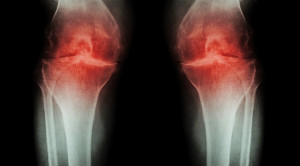

Boleh Tidaknya Berolahraga pada Osteoarthritis Lutut

Masih terdapat perdebatan mengenai apakah olahraga bermanfaat dan aman dilakukan bagi pasien osteoarthritis lutut. Osteoarthritis merupakan penyakit sendi degeneratif kronis yang ditandai...(Baca Selengkapnya)